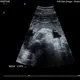

私は35週間でしたが、今日は子供の超音波検査中です。 5ポンドの14グラム。子供の大きさはどれくらいですか?

• 火曜日に私は最後の超音波、35週間を獲得し、子供の体重は5 kgでした。 6オンス。しかし、私が33週間しかない場合。この場合、良い男の子がいます。

私は37週間の超音波検査を受け、両方向に0.5マイルを獲得する能力で約6.5ポンドを獲得しました。例は安全ではありませんが、推測するのはいつでもいいことです。

• レベル3〜34週間、奨学金の奨学金は6.4です!これはあらゆる方向における人生の半分に過ぎません!今、私は7-8を意味します。彼は週に本を手に入れ、明日は37週齢です。

• 37週間。 7ポンドの7ポンドは通常、それほど正確ではありません。

• 35週間後、私は4キログラムの4グラムを持っていました。少年は、より小さなステアで9日間を測定し、20週間を過ごします。